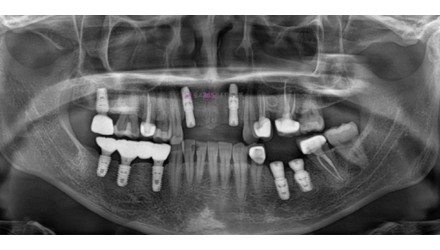

심*복 임플란트 시술 사례

전체 임플란트

2024.12.05

치료 전

2025.05.30

치료 후